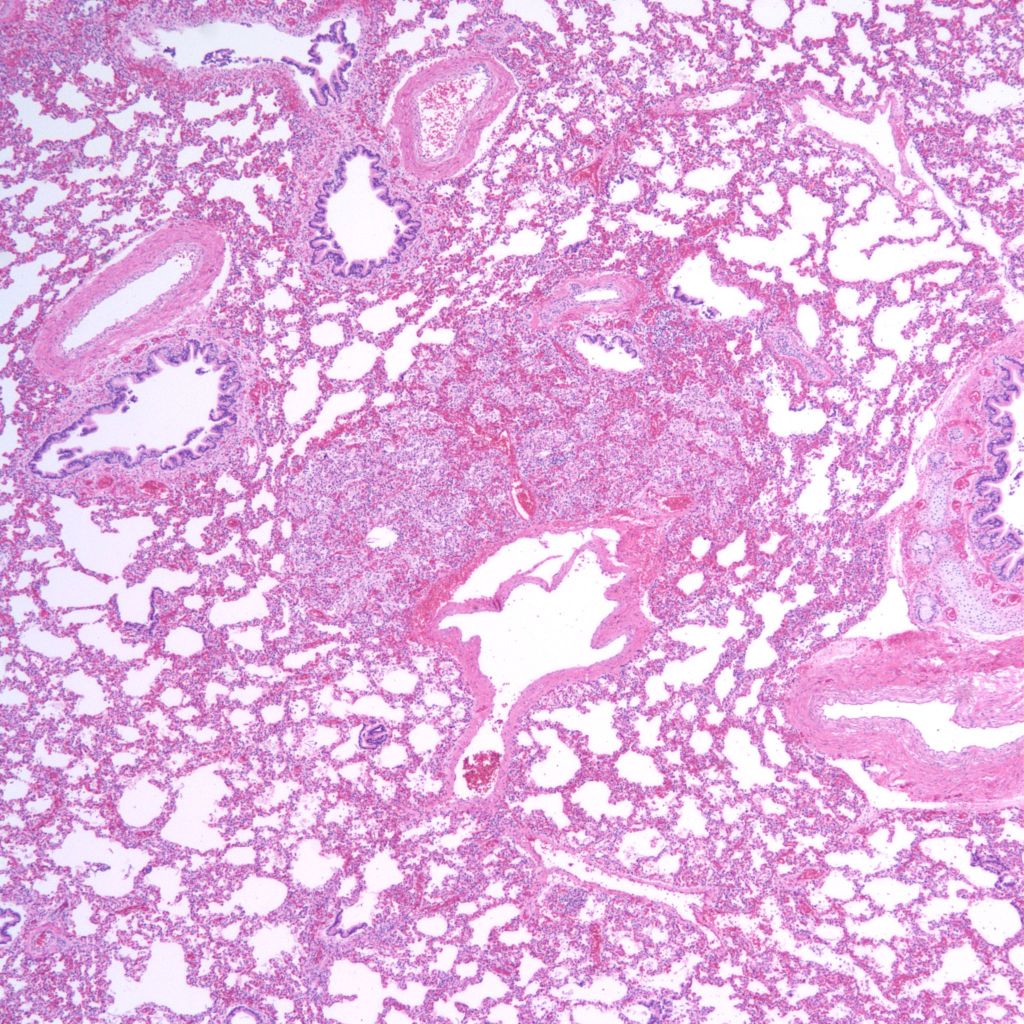

Lung development: The lungs progressively branch and then begin maturation during intrauterine development (Fig 19a, 9a-c) Lung development proceeds in orderly overlapping phases throughout gestation. These phases have classically been divided into: 1) embryonic (26 days to 6 weeks); 2) pseudoglandular (6 to 16 weeks); 3) acinar or canalicular (16 to 28 weeks); 4) saccular (28 to 34 weeks); and 5) alveolar (34 weeks to term and up until 2 years of age)16.

Descriptively, there is a regular progression of microscopic features. During the canalicular period, capillaries begin to approach the airway epithelium, beginning a progressive development of the terminal sacs with progressive thinning of the airway epithelium and protrusion of capillaries covered by thin Type 1 alveolar cells into the airspace. This progression increases the area of gas exchange. Bronchiolar type 2 cells are also maturing to produce surfactant. Multiple morphometric measures of the lung, such as volume proportion of air spaces, have good correlation with gestational age 17A simple quantitative method to estimate gestation from the lung is the radial alveolar count which is exponentially related to gestation after 18 weeks 18